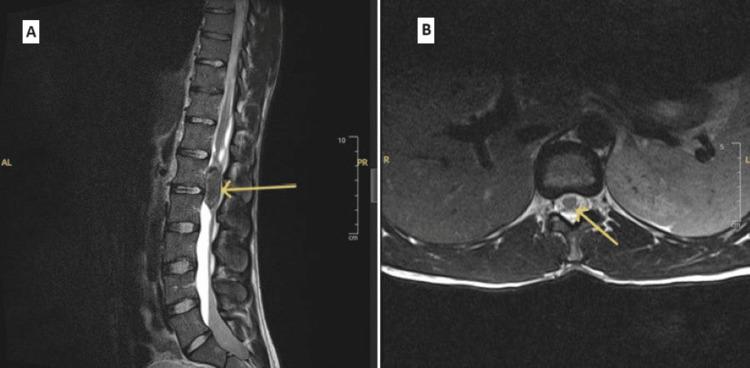

Myxopapillary ependymoma (MPE) is a rare, slow-growing tumor that commonly arises in the lumbosacral region of the spinal cord, within the filum terminale and cauda equina. The frequent presentation of MPE is back, sacral, or leg pain. The tumor's size, site, and extension usually influence these symptoms. MPE is usually evaluated using magnetic resonance imaging (MRI) because of its superior soft tissue contrast. The best treatment modality is total surgical resection, which improves the long-term survival rate, with follow-up imaging recommended to ensure total resolution. Here, we present the case of a 29-year-old male who presented with symptoms suggestive of severe neurological impairment. An MRI scan revealed an intradural lesion arising from the cauda equina with peripheral and intrathecal haemorrhage, consistent with MPE. He was managed with laminectomy and microsurgical resection of the tumor, which achieved total resection. Postoperative follow-up found gradual improvement in his symptoms, and routine surveillance imaging confirmed the complete resolution of the tumor.

摘要

黏液乳头型室管膜瘤(MPE)是一种罕见的、生长缓慢的肿瘤,通常发生于脊髓腰骶段,终丝和马尾内。MPE的常见表现为背部、骶部或腿部疼痛。肿瘤的大小、位置和范围通常会影响这些症状。由于其软组织对比度优越,MPE通常采用磁共振成像(MRI)进行评估。最佳治疗方式是手术全切,这可提高长期生存率,建议进行随访成像以确保完全切除。在此,我们报告一例29岁男性病例,该患者出现提示严重神经功能障碍的症状。MRI扫描显示一个起源于马尾的硬膜内病变,伴有周围和鞘内出血,符合MPE。他接受了椎板切除术和肿瘤显微手术切除,实现了全切。术后随访发现其症状逐渐改善,常规监测成像证实肿瘤完全消退。